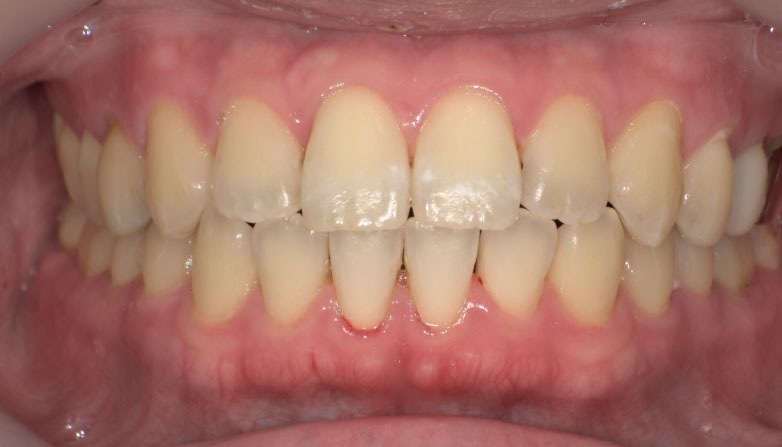

症例1

before

after

| 主 訴 | 着色が気になる |

| 治療期間 | 通院 1回 |

| 治 療 費 | 1回 7,700〜11,000円(税込) |

| 治療内容 | PMTC |

| 治療のリスク | 歯自体の色を白くすることはできない。 歯と歯の間や強い着色などは落とすことが出来ないことがある。 しばらくすると再び着色することがある。 |